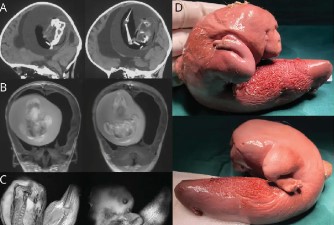

ইভিএম নিউজ ব্যুরো, ১০ মার্চঃ জন্মের পর থেকেই মাথাটার আকার স্বাভাবিকের থেকে অনেকটাই বড়। পরে অসহ্য যন্ত্রণায় হাসপাতালে নিয়ে যাওয়া হয় চিনের এক বছর একের শিশুটিকে। পরে সিটি স্ক্যান করে দেখা যায় অস্বাভাবিক এক কাণ্ড। শুনলে অবাক হবেন শিশুটির মাথাতে বেড়ে উঠছিল পরস্পর দুটি ভ্রূণ। যেটি অমেরিকান অ্যাকাডেমি অব নিউরোলজি জার্নালে ছাপাও হয়েছে ঘটনাটি। জেনে নেওয়া যাক ফিটাস ইন ফিটু